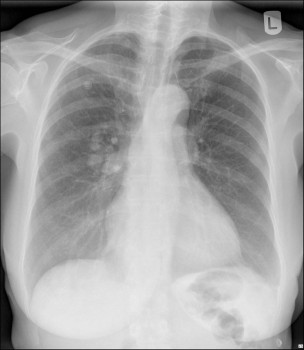

Haar huisarts verwijst haar naar de Eerste Harthulp, waar de uitslag van het bloedonderzoek (troponine en d-dimeer) normaal blijkt te zijn, afgezien van een hypoxemie (pO2 58 mmHg; normaal 75-100 mmHg). Op de thoraxfoto zijn verdichtingen te zien [figuur 1], die na hogeresolutiecomputertomografie op pulmonale arterioveneuze malformaties blijken te berusten [figuur 2]. Er is tevens sprake van een forse rechts-links shunt. De patiënte geeft aan vaak bloedneuzen te hebben, net als haar jongere broer. Een oudere broer blijkt vroeger geopereerd te zijn aan een pulmonale malformatie.

X-thorax: diverse intrapulmonale verdichtingen mediaal in de rechter long

Figuur 1 | X-thorax: diverse intrapulmonale verdichtingen mediaal in de rechter long